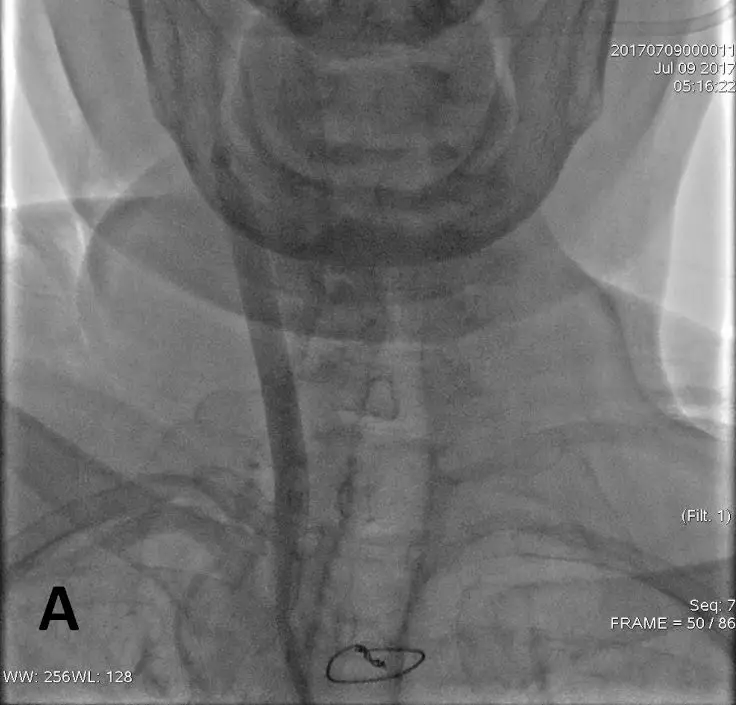

8F指引导管联合6F Navien中间导管,冒烟证实,右侧CCA中段以远未见显影(A),造影证实,右侧ICA窦部以远未见显影(B)

8F指引导管联合6F Navien中间导管,通过中间导管造影,提示ICA眼动脉段以远未见显影